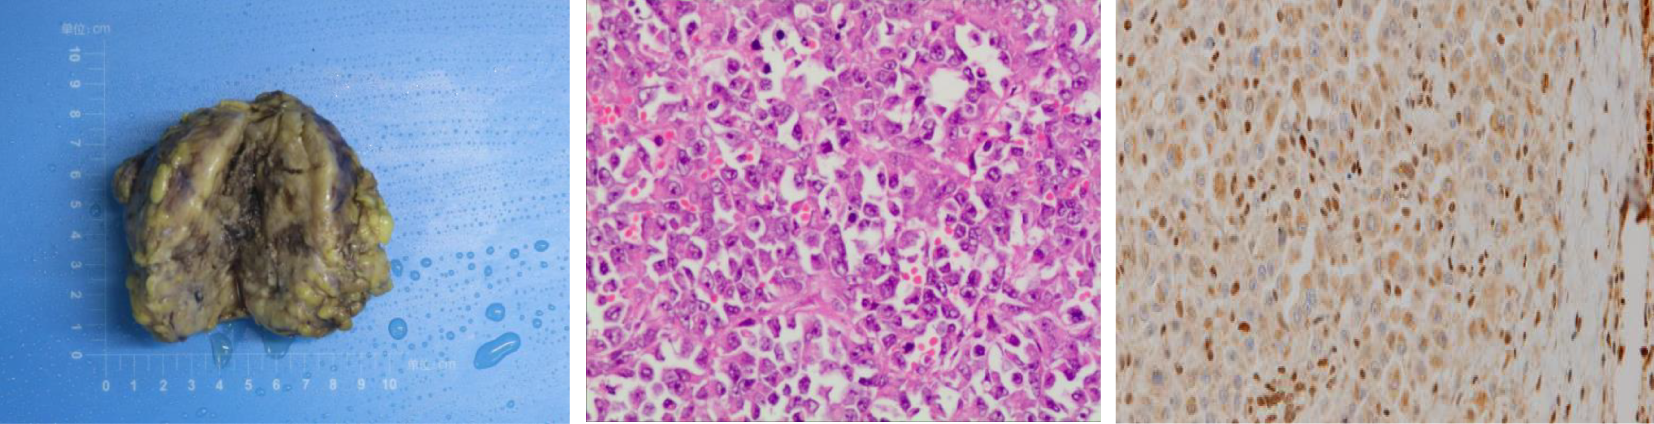

Figure 2

Left: Gross appearance of a local resection specimen showing a tumor with a grey-white cut surface. Middle: Microscopic appearance. Tumour is composed of epithelioid cells. H and E, x 400. Right: Loss of INI-1 expression in nuclear of tumor cells.

Based on the results from ultrasonography combined with fetal heart electronic monitoring and clinical evaluation (cervical ripening, pregnant women’s weight, and uterine height), experts in obstetrics and neonatology suggested that there was a high possibility of fetal maturity although amniocentesis was not conducted. Prophylactic corticosteroids for facilitation of fetal lung maturation were not administered due to their controversy from 34 to 36 + 6 weeks of gestation. According to guidelines from the American College of Obstetricians and Gynecologists (7), corticosteroids are recommended for women from 34 to 36 + 6 weeks of gestation who may have premature birth within 1 week. Subsequently, the obstetrics team performed preterm cesarean section, and the gynecology team performed radical local resection of the lesion on the left labia majora and left inguinal lymphadenectomy at 36 weeks and 4 days of gestation. Final pathology of the specimen demonstrated a 7-cm-sized ES with the infiltration of surrounding adipose tissue, and no necrosis, hemorrhage, or venous invasion were identified. Surgical resection margins were clear and free of tumor (distance of 2 cm from biopsy lesion). There were no lymphovascular emboli, perineurial invasion, or regional lymph node metastasis. Immunohistochemically, the tumor cells were positive for EMA, SMA, IMP3, and vimentin, while negative for S100, Desmin, Myogenin, MyoD1, and CD34. INI-1 expression was lost in tumor cells (Figure 2). Morphologically, it is necessary to distinguish ES from other epithelioid-looking tumors such as epithelioid peripheral nerve sheath tumor, epithelioid leiomyosarcoma, epithelioid angiosarcoma, rhabdomyosarcoma, malignant melanoma, and poorly differentiated squamous cell carcinoma. The diagnosis can only be confirmed with immunohistochemical staining, and the case was sent to a pathologist, for a second opinion, who agreed with the diagnosis of ES. The final diagnosis was proximal-type vulvar ES. The female newborn weighed 2,900 g, and the Apgar score was 9/10 (at 1 min/5 min). The newborn was not incubated and subsequently discharged uneventfully.